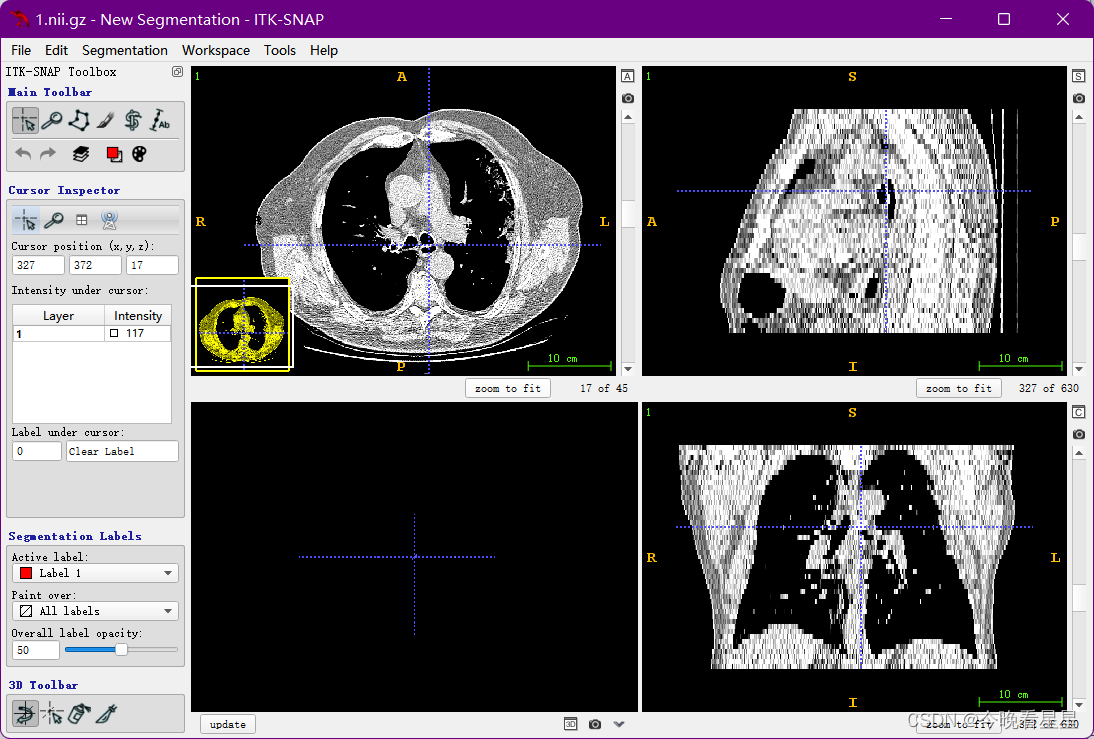

1.1 ITK-Snap视图介绍

在刚开始使用软件的时候,可能上来就被该软件的视图搞蒙了,类似于咱们数学上的三视图,但是他是从CT扫描的视角观察的

三个切片窗口分别为:

- 轴向面(Axial)

- 矢状面(Sagittal)

- 冠状面(Coronal)

常用的有轴向面与冠状面,可以帮助我们进行空间上的定位与标注

显示一个主图

- 对当前进行截图

- 使用大小